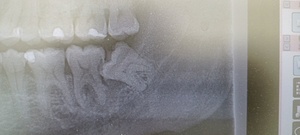

少し見えて横になった親知らず

親知らずのレントゲン

親知らずの歯はどこの場所?

親知らずは、永久歯(大人の歯)の中で最後に発育する歯で、中切歯(最前方の前歯)から数えて8番目の最後方歯に位置しています。

18歳前後から生えてくるので、20代前半までに抜歯するのがおすすめです。

親知らずは必ずしも抜かなければいけないものではありませんが、痛みや腫れを繰り返す場合や、他の歯に影響を及ぼしてしまう可能性がある場合は抜歯を行う必要があります。

親知らずが腫れる理由は?

親知らずの半分が歯ぐきの中に埋まっていたり、傾いていたりするので、親知らずの周りの歯ぐきの“くぼみ”に歯垢(プラーク、細菌)が溜まりやすく不潔となり、体調を崩し免疫力が落ちると、そこから炎症を起こし、周辺の歯ぐきが腫れてきます。

親知らずを原因とする歯周炎は「智歯周囲炎」と呼ばれ、通常のむし歯による歯周炎に比べ、炎症の程度が強いのが特徴です。このため、痛みがひどく、頬まで腫れた、口が開きにくいといった重い症状を引き起こしやすくなります。